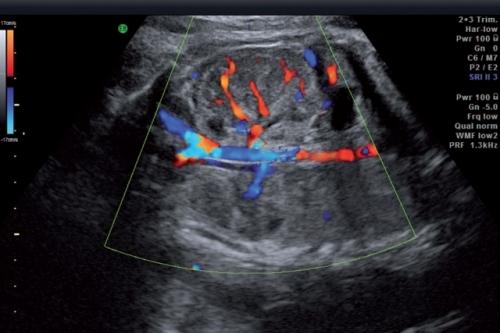

Кровоток в артерии пуповины

Процедура проводится на обычном аппарате, предназначенного для УЗИ, оснащенного специальным программным обеспечением. Обычное УЗИ показывает состояние и структуру мягких тканей внутренних органов, отклонения от нормы. Допплерография позволяет оценить движущиеся объекты, например, движение крови по венам и артериям. Именно особенности кровяного потока в системе «мама-плод» изучает врач-гинеколог при получении результатов доплера.В основе УЗИ Доплера (допплерометрия), назначающегося почти всем беременным, лежит метод изменения частоты сигнала при отражении от движущихся частиц.Волны, излучающиеся ультразвуковым датчиком, отражаются от движущихся частиц гораздо чаще, чем от неподвижных. Но кровь движется по сосудам в разных направлениях: частота отраженных волн от частиц, движущихся от датчика, увеличивается, а к датчику – уменьшается, что даёт представление о скорости кровотока.Результат изменения параметра представляется на экране монитора, где разными цветами (синим и красным) показана схема движения крови по всей кровеносной системе плода.

Артерии пуповины (a. umbilicalis). Для получения истинных результатов, исследование должно проводиться только в то время, когда малыш находится в состоянии покоя, и только когда его ЧСС находится в пределах 120-160 ударов в минуту. Ведь физиологически так заложено, что при повышении ЧСС происходит снижение ИР в артерии пуповины, и наоборот, при снижении ЧСС происходит увеличение ИР.

Наибольшее распространение при оценке характера кровотока в артериях пуповины получил индекс резистентности. Показатели в обеих артериях пуповины должны быть практически одинаковы.